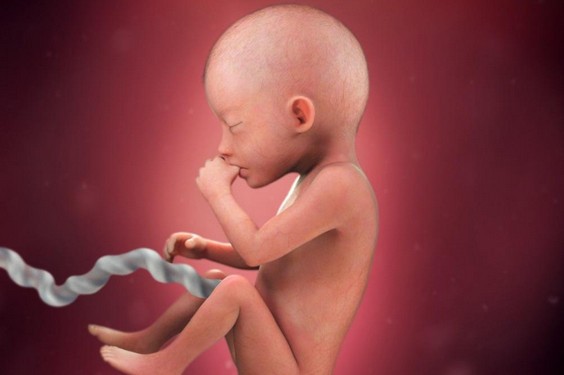

الأسبوع الخامس عشر

يحدث خلال هذا الأسبوع تطور في نمو جلد الجنين وشعر الرأس والحاجبين وتبدأ الأذن في استقرارها بمكانها الصحيح، كما يتطور نمو الهيكل العظمي للجنين ويبدأ الجنين بتحريك بعض أعضاؤه مثل الفمن الرأس، اليدين والقدمين.

الأسبوع السادس عشر

خلال هذا الأسبوع تنتصب رأس الجنين وتنمو عضلات وجهه بشكل واضح ويصبح قادر على التحديق بعينه وقطب حاجبه كما يبدأ في مص الإبهام ويصبح وزنه في نهاية هذا الأسبوه 110 جم.